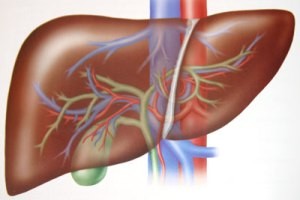

برطرف نمودن چاقی و اضافه وزن ، کنترل چربیهای خون، کنترل قند خون و افزایش فعالیت بدنی به کنترل این بیماری کمک شایانی می نماید. قطعا یک رژیم غذایی متعادل برای تخفیف و درمان بیماری کبد چرب ضروری است. کبد یک عضو حیاتی در بدن است چرا که هر آنچه که می خورید (چه خوب و چه بد ) رهسپار کبد می گردد و اگر رژیم غذایی شما نامناسب باشد سلامت کبد شما را در مخاطره قرار می دهد.